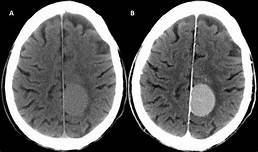

Paciente com quadro de cefaleia progressiva associada a déficit focal, HAS, bradicardia, arritmia respiratória, papiledema, sonolência, estrabismo convergente e vômitos em jato…

Diagnósticos …

cefaleia progressiva + HIC + sinal focal…

Neoplasias (sem febre)

Abscesso (com febre)

Paciente com quadro de cefaleia progressiva sem déficits ficais, associada a HAS, bradicardia, arritmia respiratória, papiledema, sonolência, estrabismo convergente e vômitos em jato…

Hidrocefalia

cefaleia progressiva + HIC + sem sinal focal…